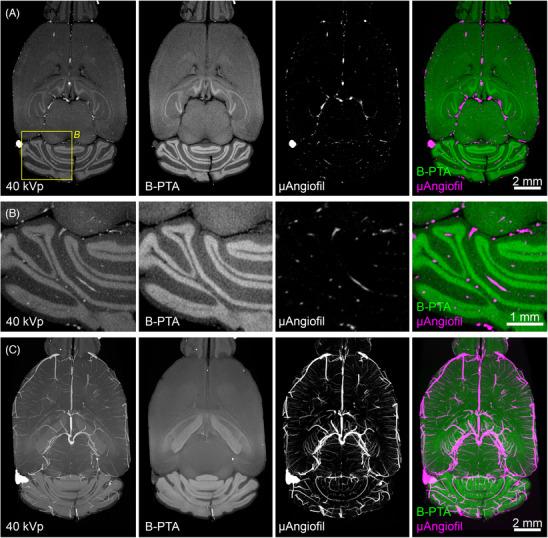

Ex vivo x-ray angiography provides high-resolution, three-dimensional information on vascular phenotypes down to the level of capillaries. Sample preparation for ex vivo angiography starts with the removal of blood from the vascular system, followed by perfusion with an x-ray dense contrast agent mixed with a carrier such as gelatine or a polymer. Subsequently, the vascular micro-architecture of harvested organs is imaged in the intact fixed organ. In the present study, we present novel microscopic dual-energy CT (microDECT) imaging protocols that allow to visualise and analyse microvasculature in situ with reference to the morphology of hard and soft tissue. We show that the spectral contrast of µAngiofil and Micropaque barium sulphate in perfused specimens allows for the effective separation of vasculature from mineralised skeletal tissues. Furthermore, we demonstrate the counterstaining of perfused specimens using established x-ray dense contrast agents to depict blood vessels together with the morphology of soft tissue. Phosphotungstic acid (PTA) is used as a counterstain that shows excellent spectral contrast in both µAngiofil and Micropaque barium sulphate-perfused specimens. A novel Sorensen-buffered PTA protocol is introduced as a counterstain for µAngiofil specimens, as the polyurethane polymer is susceptible to artefacts when using conventional staining solutions. Finally, we demonstrate that counterstained samples can be automatically processed into three separate image channels (skeletal tissue, vasculature and stained soft tissue), which offers multiple new options for data analysis. The presented microDECT workflows are suited as tools to screen and quantify microvasculature and can be implemented in various correlative imaging pipelines to target regions of interest for downstream light microscopic investigation.

离体X射线血管造影可提供高分辨率的三维信息,显示直至毛细血管水平的血管表型。离体血管造影的样本制备首先要从血管系统中去除血液,然后用与明胶或聚合物等载体混合的X射线高密度造影剂进行灌注。随后,对完整固定器官中采集的器官的血管微结构进行成像。在本研究中,我们提出了新颖的微观双能CT(microDECT)成像方案,该方案能够参照硬组织和软组织的形态原位可视化和分析微血管。我们表明,灌注标本中µAngiofil和硫酸钡微球的光谱对比度可有效区分血管与矿化骨骼组织。此外,我们展示了使用已有的X射线高密度造影剂对灌注标本进行复染,以描绘血管以及软组织的形态。磷钨酸(PTA)用作复染剂,在µAngiofil和硫酸钡微球灌注的标本中均显示出出色的光谱对比度。引入了一种新颖的索伦森缓冲PTA方案作为µAngiofil标本的复染剂,因为使用传统染色溶液时聚氨酯聚合物容易出现伪影。最后,我们证明复染后的样本可以自动处理成三个单独的图像通道(骨骼组织、血管和染色的软组织),这为数据分析提供了多种新选项。所展示的microDECT工作流程适合作为筛选和量化微血管的工具,并且可以在各种相关成像流程中实施,以针对感兴趣区域进行下游光学显微镜检查。